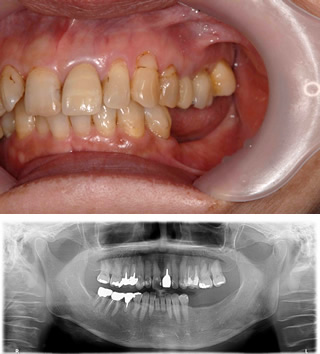

インプラント治療例